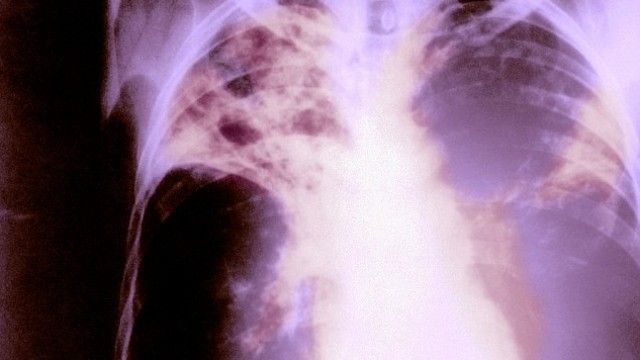

Maqedoni, numri i rasteve me tuberkuloz në rënie të vazhdueshme

Numri i rasteve me tuberkuloz në vendin tonë është në rënie të vazhdueshme, por sëmundja është ende prezente. Këtë e kanë konfirmuar për AIM nga Spitali i Sëmundje të Mushkërive tek Fëmijët “Kozle” dhe Instituti i Sëmundjeve të Mushkërive dhe Tuberkulozit.

Drejtori i Spitalit të Sëmundjeve të Mushkërive tek Fëmijët “Kozle”, doktor Besnik Zeqiri, thotë se në Institut mesatarisht çdo vit kanë nga 10 deri në 12 fëmijë.

“Për shkak të pandemisë së Kovid-it, këto shifra ishin më të ulëta në dy vitet e fundit, nga pesë deri në tetë fëmijë për çdo vit. Këtë vit për dy muaj kemi diagnostikuar 11 raste me tuberkuloz dhe rreth 20 me infeksion latent të tuberkulozit”, tha për AIM, drejtori i Spitalit, Zeqiri.

Ai sqaroi se në repartin e tyre të tuberkulozit, aktualisht në spital po trajtohen gjashtë fëmijë dhe të gjithë janë në gjendje stabile.

“Për parandalimin e kësaj sëmundjeje kërkohet vaksinimi me vaksinën BCG pas lindjes, zbulimi i të sëmurëve, kryesisht të rriturve me TBC pulmonar që përhapin infeksionin dhe më e rëndësishmja zbulimi i kontakteve dhe vëzhgimin e tyre, veçanërisht fëmijët që kanë nevojë për terapi të përshtatshme mbrojtëse, si të mos zhvillohet sëmundja”, theksoi Zeqiri.

"Ndonëse është një sëmundje e shërueshme dhe e parandalueshme, 141 vjet nga zbulimi i agjentit shkaktar të tuberkulozit, 75 vjet nga zbulimi i barnave efektive, tuberkulozi është ende një problem shëndetësor global. Është i pranishëm në të gjitha vendet dhe të gjitha grupmoshat. Çdokush mund të sëmuret nga tuberkulozi. Megjithatë, grupe të caktuara njerëzish janë në rrezik të shtuar për tu infektuar, përkatësisht njerëzit që kanë qenë në kontakt të drejtpërdrejtë me një të sëmurë me tuberkuloz, anëtarët e familjes, veçanërisht fëmijët, pastaj personat që jetojnë me HIV, gjithashtu njerëzit që jetojnë në kolektivë burgjesh si strehimoret për migrantët dhe të pastrehët, burgjet, repartet psikiatrike, personat që jetojnë me mjete materiale nën kufirin e varfërisë, si dhe pacientët kronikë me imunitet të reduktuar, ku nuk ka mundësi për parandalimin e sëmundjes – diabetikët, pacientët me kortikoterapi afatgjatë, pacientët nga sëmundjet malinje”, theksoi Zejneli.